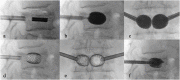

Vertebral fracture (VF) is a common condition with >160,000 patients affected every year in North America and most of them with affected lumbar vertebrae. The management of VF is well known and defined by many protocols related to associated clinical neurological symptoms, especially in case of the presence or absence of myelopathy or radicular deficit. In this article, we will explore the percutaneous stabilization of the lumbar spine by showing the newest approaches for this condition.